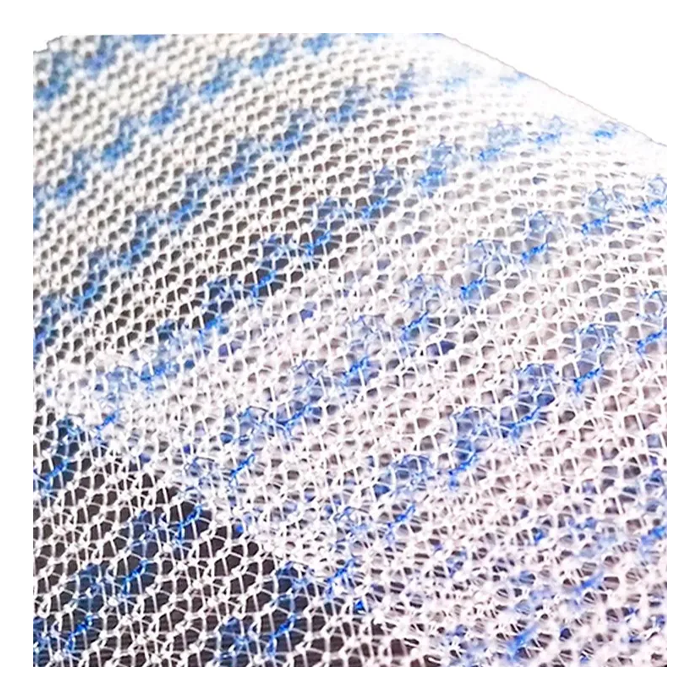

Эндопротез-сетка (сетка хирургическая) полипропиленовый для восстановительной хирургии ЭСФИЛ тяжелый, 8х12 см, Линтекс

Эндопротез-сетка полипропиленовая ЭСФИЛ тяжелый для восстановительной хирургии

Представляем вашему вниманию высококачественный хирургический имплантат — эндопротез-сетку полипропиленовую ЭСФИЛ тяжелый от известного производителя «Линтекс». Это современное решение для пластики и укрепления тканей в абдоминальной и тазовой хирургии, разработанное для обеспечения надежного и долговечного результата.

Сетка ЭСФИЛ тяжелый размером 8х12 см — это монофиламентный полипропиленовый сетчатый эндопротез с увеличенной плотностью и массой. Его ключевая особенность — высокая механическая прочность при минимальной ригидности, что позволяет эффективно закрывать обширные дефекты тканей, обеспечивая физиологичное и анатомичное восстановление.

- Отличная интеграция с тканями: Макропористая структура монофиламентной сетки способствует свободному прорастанию соединительной ткани, обеспечивая прочное сращение и снижая риск осложнений.

Благодаря макропористой структуре (размер пор более 75 мкм) сетка свободно инфильтрируется макрофагами, фибробластами и коллагеновыми волокнами. Это приводит к образованию прочного соединительнотканного рубца, который и составляет основу несущего каркаса.